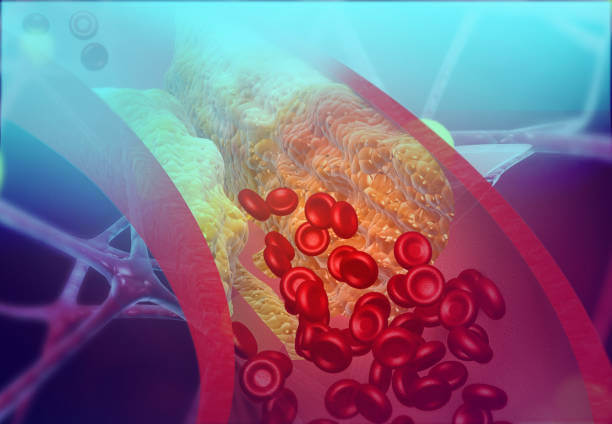

콜레스테롤이 혈관 벽에 쌓이면 "플라크" 라고 불리는 지방 침착물이 형성됩니다. 이 플라크는 동맥 벽 내부를 좁게 만들어 혈액 흐름을 제한합니다. 협심증은 주로 심장에 산소와 영양분을 공급하는 관상동맥에서 발생하므로, 관상동맥에 플라크가 형성되면 심장에 충분한 혈류가 공급되지 못해 협심증 증상이 발생할 수 있습니다.

플라크가 점차 성장하면서 혈관 내부를 좁혀나갑니다. 이로 인해 혈액 흐름이 제한되고 심장에 산소와 영양분을 공급하는 관상동맥의 혈류가 감소합니다.